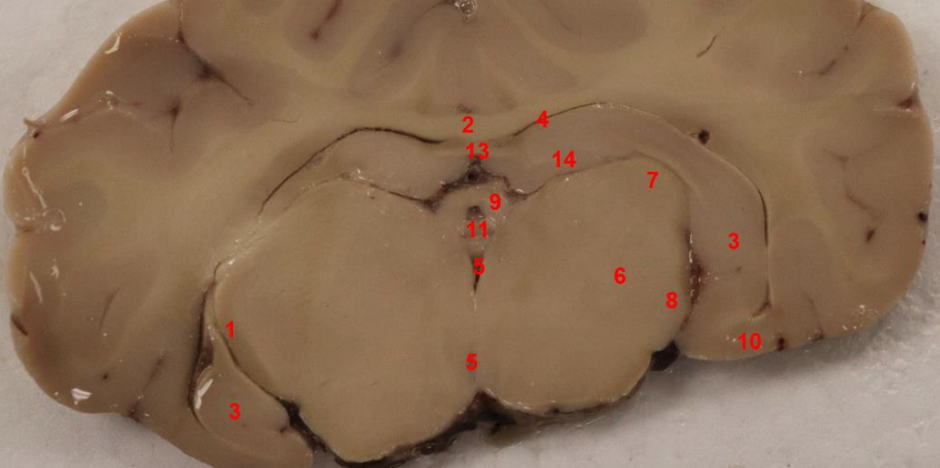

what area is this

hypothalmus

what ventricle is this

3rd ventricle

internal capsule

what nuclei is this

caudate nucleus

fimbria

Fornix

lateral ventricle

subcallosal fasciculus

what is this

optic tract

hippocampus

what cortex is this, function

entorhinal cortex , spatial navigation, memory formation, and consolidation

mamillary bodies

what tract is this

hippocampal commissure

what area is this?

Denate Gyrus

Habenula

mammillothalmic tract

entorhinal cortex

subiculum

lateral geniculate nucleus, filters visual signals, mediates attention by prioritizing important information,

what is this (13)

hippocampal commisure

LGN

enthorinal cortex

MGN

thalamus